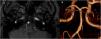

A brain CT scan and CT angiography revealed right occipital lesions (Fig. 1A) and a linear filling defect in the basilar artery (Fig. 1B). A transoesophageal echocardiography study showed small-sized patent foramen ovale. Blood testing revealed no serological or autoimmune alterations. An MRI study identified multiple subacute ischaemic lesions in the right occipital parasagittal and occipitotemporal regions, as well as in the right middle cerebellar peduncle. A 3D time-of-flight (TOF) sequence showed asymmetry of the posterior inferior cerebellar arteries, with the left artery being larger, and asymmetry of the vertebral arteries, with the right artery showing smaller diameter and progressively reduced blood flow in the distal third; a focal filling defect in the inferior third of the basilar artery was observed, which was compatible with basilar web, fenestration, or (less probably) dissection of the artery (Fig. 2A).

Figure 1.

Axial CT scan performed at the time of diagnosis. (A) We observed 2 areas of parenchymal hypodensity in the right occipital region, both showing cortico-subcortical involvement and recent haemorrhagic foci in the interior. (B) After contrast administration, we observed a non-specific linear filling defect in the basilar artery; no other relevant alteration was observed in the supra-aortic trunks or intracranial arteries.